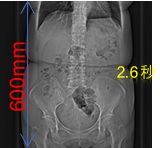

高速で230mm/秒で撮影することができ、例としておなか60cmの範囲を撮影するとした場合、約3秒の息止めで撮影することが可能です(検査の種類、目的により異なります)

高速撮影